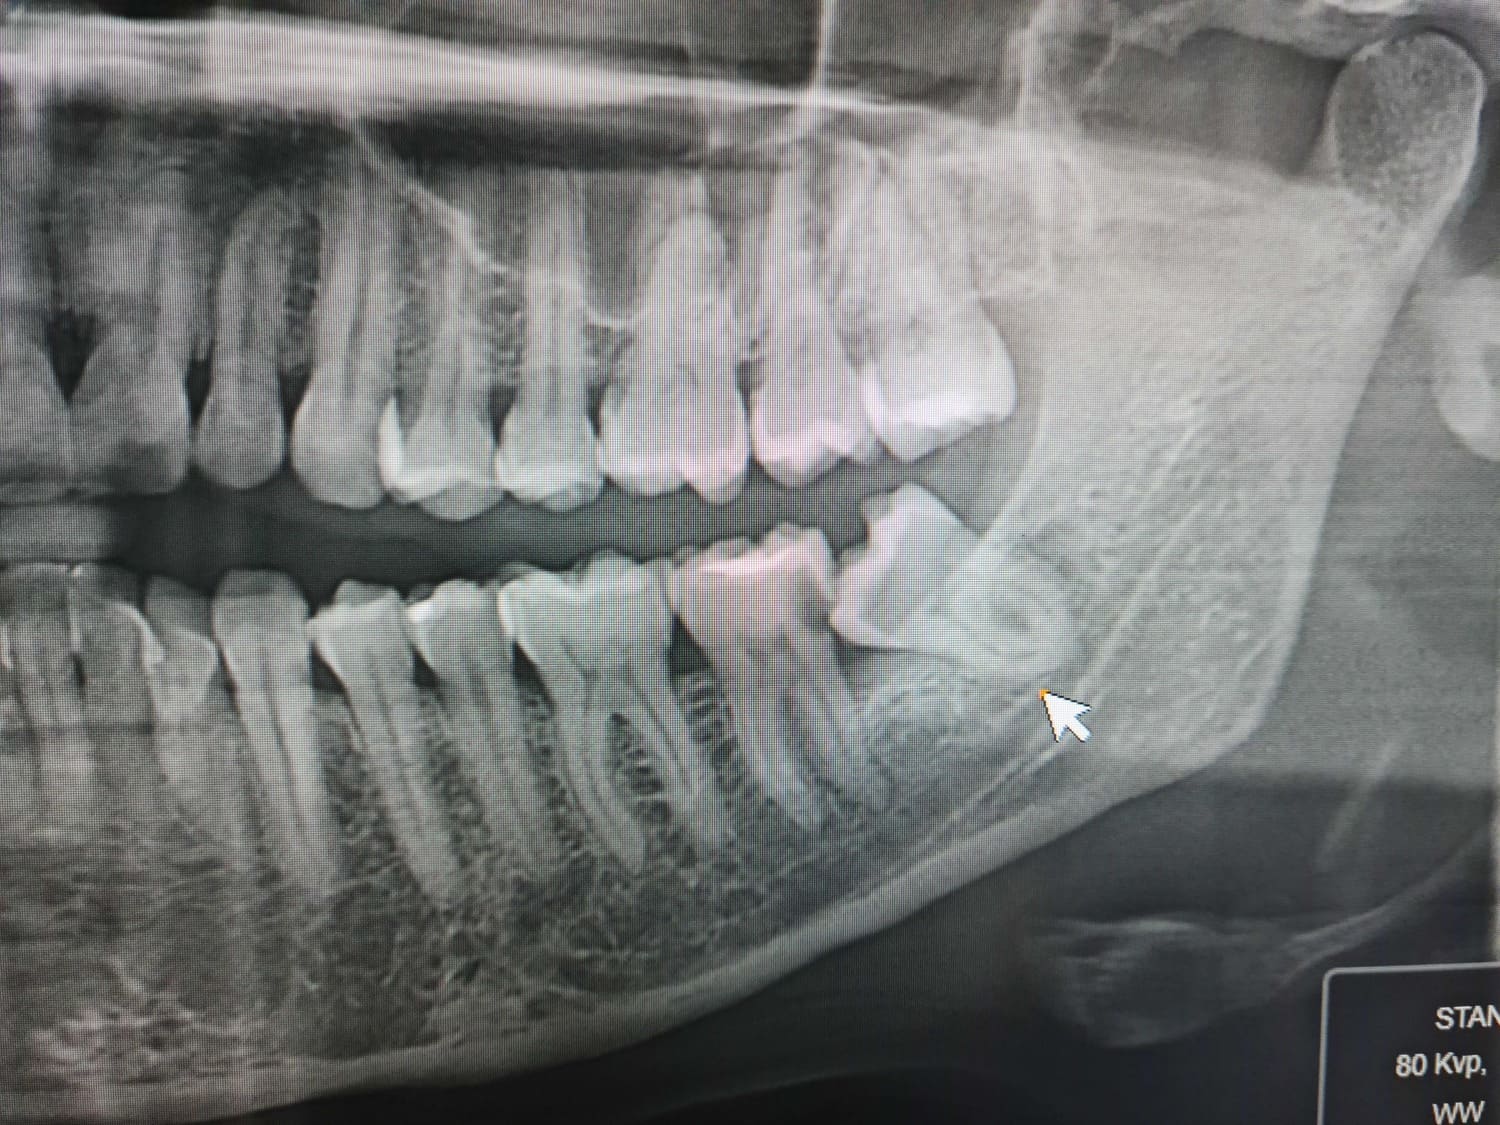

Jak ocenić stopień trudności usunięcia trzecich zębów trzonowych na podstawie badania klinicznego i radiologicznego.